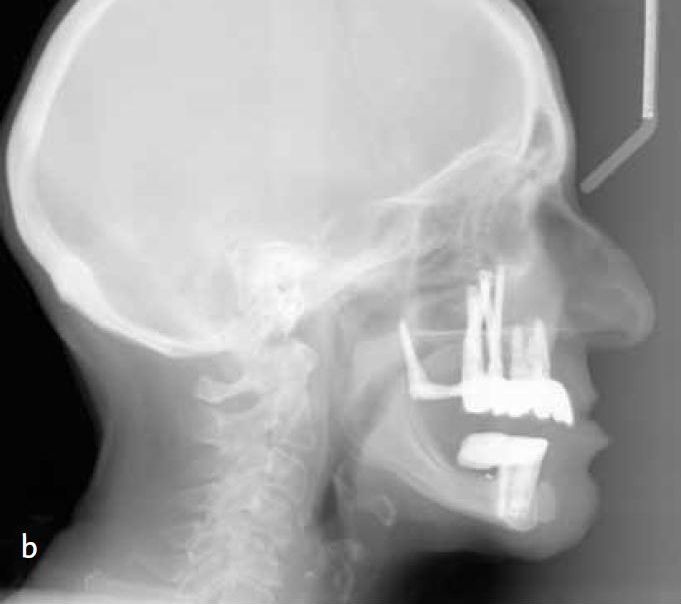

A primary contra-indication for a fixed maxillary implant supported prosthesis is severe anterior bone loss. Why? Well you can not have both a bulk of material to properly support the lip and make the restoration cleansable. In these types of cases either a Marius bridge or an overdenture is called for. Maybe the patient signed a form saying she would except a sunken lip in exchange for having something that she can not take out, but I doubt that. Now they wisely never show a face shot or profile shot, but you can see the significant loss of lip support in her lateral cephs. I immediately noticed the deficient lip on the cover and when I read the title I knew exactly why it was that way.

This case would have been a slam dunk if the surgeon had placed implants where they should have been. It appears to me even if the restorative doc was presented with this case to start he should have insisted on an implant in #4 also, there appears to be room. They state in the article that she was class III to start with. I would like to see a lateral ceph because I am guessing she is class III because that is the pattern of bone loss. I also am guessing the lowers were restored right above the existing resorbed bone making it very difficult to restore the uppers properly (I do not know that for sure but is is highly likely and would fit with the poor planning pattern seen in this case). Against a mand implant supported prosthesis this case is at a much higher risk of failure.